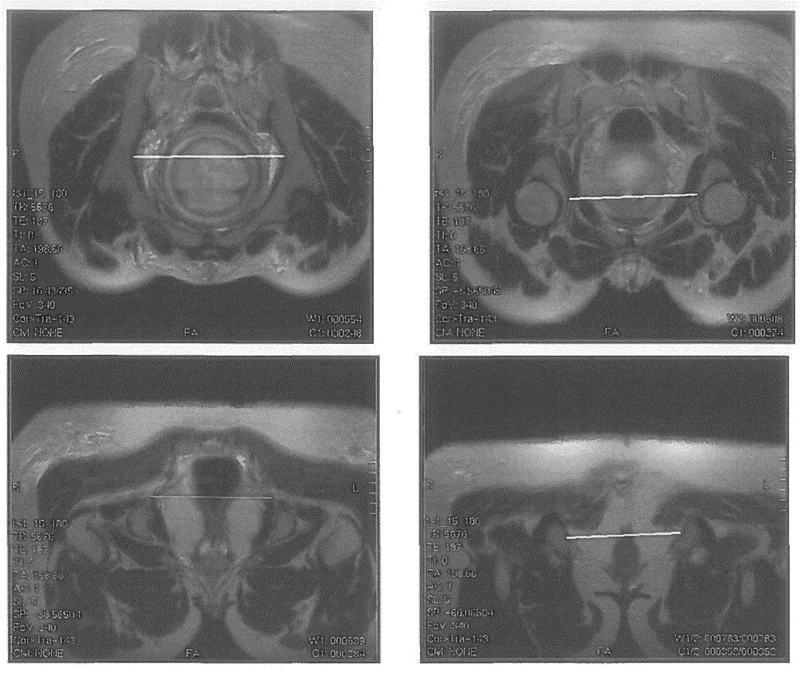

МР-пельвиметрия - магнитно-резонансная пельвиметрия, измерение размеров полости таза с помощью магнитно-резонансной томографии.

Низкий рост, уменьшение межвертельного размера таза, поперечного и продольного размеров пояснично-крестцового ромба Михаэлиса, отношение роста беременной к высоте дна матки = менее 4,7 значимо чаще встречаются при клинически узком тазе [9], [10], [11], [12], [13]. Поэтому их измерение используют в качестве скринингового метода при его прогнозировании [14], [15]. Данные компьютерной томографии показали, что женщины с уменьшенным прямым размером выхода таза и узким лонным углом имеют повышенные риски затрудненных родов, требующих оперативного родоразрешения [16]. В современной клинической практике в качестве дополнительного объективного метода оценки размеров полости таза используют магнитно-резонансную пельвиметрию, которая не оказывает лучевой нагрузки [17], [18].

Комментарий. МР-пельвиметрия является радиационно-безопасным, объективным методом оценки размеров полости таза. При этом степень уменьшения размеров таза по данным МРТ обратно пропорциональна частоте кесарева сечения, влагалищных родоразрешающих операций и травм промежности [60], [61]. Применение МР-пельвиметрии целесообразно в группе риска, показания к ее проведению определяются по результатам клинического обследования (см приложение). Рутинное применение МРТ не рекомендуется, так как не является методом выделения группы женщин, подлежащих дородовому оперативному родоразрешению [62].

• Рекомендовано женщинам, у которых по заключению консультативного осмотра в КДЦ акушерского стационара третьего уровня определены показания к уточнению размеров таза для выбора способа родоразрешения, проводить МР-пельвиметрию [17], [18], [59].Уровень убедительности рекомендаций В (уровень достоверности доказательств - 3).